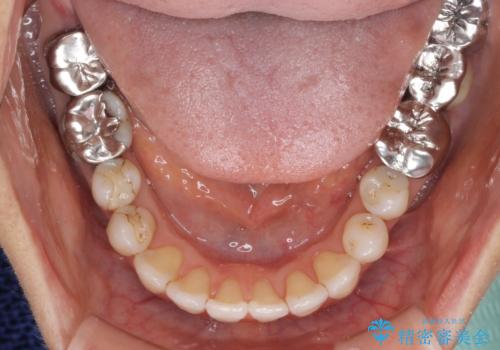

前歯の突出感と上下の隙間 インビザラインによる矯正治療

- 前歯の上下スペースと前歯の隙間を気にして来院された患者様です。

インビザラインにより上下の前歯の隙間を閉じながら、IPRを用いて口元の突出感を合わせて改善していくこととしました。

上下の隙間に舌が入り込むことが、すきっ歯やオープンバイトの原因であったため、舌の筋肉のトレーニングも並行して行い、後戻りの抑制を図りました。